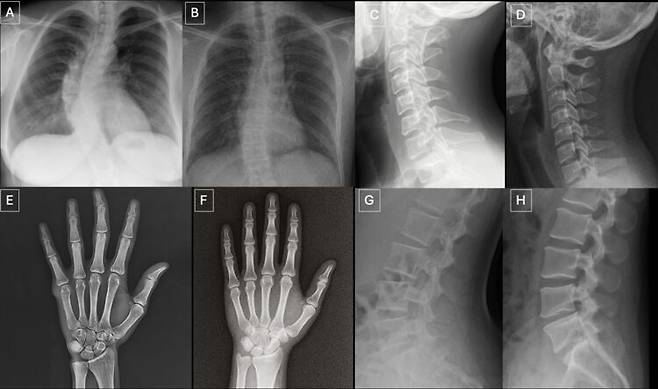

AI가 만든 가짜 X-선 사진… 전문의 10명 중 4명만 구별했다

지피티·제미나이·라마 등으로 이미지 생성

미국에서 영상의학 전문의들에게 실제 환자의 X-선 사진과 AI가 생성한 가짜 영상을 각각 보여줬더니 사전 고지 없이도 스스로 '가짜 영상'을 구별해낸 전문의의 비율은 41%로 나타났다. 절반이 안되는 수치다. AI 영상이 포함됐다고 알려준 상태에서 가짜 영상과 실제 사진을 정확하게 구별해낸 비율은 75% 수준이었다.

연구는 3단계로 나눠 진행됐다. 1단계에서는 AI 생성 이미지 77장과 진짜 실제 이미지 77장 등 154장을 영상의학과 전문의들에게 제시해 화질을 평가하고 진단을 내리게 했다.

2단계에선 영상의학 전문의들에게 AI 이미지가 포함됐음을 알린 뒤 무작위로 제시된 X선 사진이 지피티-4o로 생성된 것인지 실제 이미지인 지를 판별하게 했다. 이와 함께 4가지 AI 프로그램에 같은 판별 작업을 하게 했다. 3단계에선 추가로 AI 합성 55장과 실제 영상 55장 등 모두 110장의 흉부 X선 사진을 제시해 전문의와 AI의 판독 능력을 통계적으로 분석했다.

사전정보를 제공하지 않은 상태에서 영상 전문의 17명 중 7명(41%)이 데이터 중에 AI 생성 영상이 있음을 스스로 알아차렸다. 일부 영상이 AI 합성이라는 사실을 알려준 뒤 전문의들에게 진짜와 가짜를 골라내게 했더니 평균 적중률이 75%로 나타났다. 민감도(진짜를 진짜로 골라낸 비율) 69%. 특이도(가짜를 가짜로 골라낸 비율) 80%였다.

진짜와 가짜를 판별하지 못하는 것은 AI 프로그램도 마찬가지였다. AI 프로그램에 진짜 영상과 AI 합성영상을 제시해 구별해보라고 했더니 지피티-4o는 85%, GPT-5는 83%, 라마4매버릭은 59%, 제미나이2.5프로는 56%를 각각 실제 영상과 구별했다.

부자연스러운 조직 질감, 매끄러움 등 AI 가짜영상 구분법 발견

연구팀은 AI 가짜 영상을 분석한 결과 뼈가 지나치게 매끄럽다든지, 조직의 질감이 미미하게 부자연스럽다든지, 균일한 노이즈(불필요한 알갱이나 거친 입자, 불규칙한 색상이나 얼룩)가 나타나는 등 공통점을 발견할 수 있었다고 지적했다. 이런 노하우를 축적해 교육·수련 등에 사용할 수 있다는 의미다.